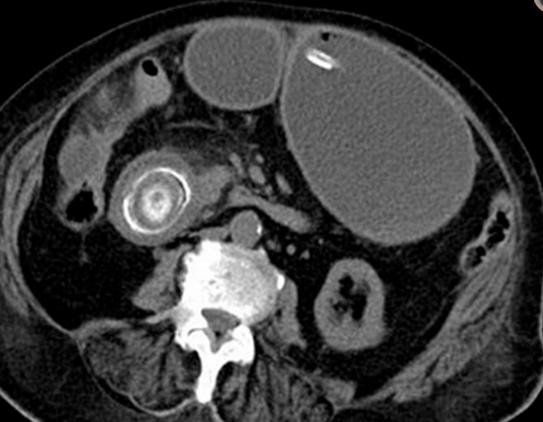

Bouveret 综合症 是由胆道系统结石通过胆肠瘘或经 Oddi 括约肌进入胃肠道引起的机械性消化道梗阻,常发生于老年女性中。 临床症状包括恶心呕吐、腹痛等。 CT 表现为肠管积液积气扩张,异位结石和胆道系统积气。

老年女性,腹痛、呕吐就诊。CT 平扫示胃腔扩张,十二指肠降部腔内见高密度结石。

老年女性,右上腹疼痛、呕吐。CT 增强示十二指肠球部结石,十二指肠球部及胆囊相通,存在瘘。